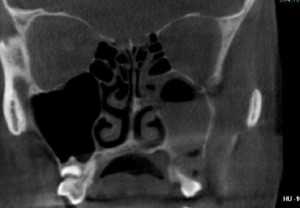

ΠΠ° ΠΎΡΠΌΠΎΡΡΠ΅ Π²ΡΠ°Ρ ΡΡΠΎΡΠ½ΡΠ΅Ρ ΡΠΈΠΌΠΏΡΠΎΠΌΡ, Π°Π½Π°ΠΌΠ½Π΅Π·, ΡΠΌΠΎΡΡΠΈΡ Ρ ΠΏΠΎΠΌΠΎΡΡΡ ΡΠΏΠ΅ΡΠΈΠ°Π»ΡΠ½ΡΡ Π·Π΅ΡΠΊΠ°Π» ΡΠ»ΠΈΠ·ΠΈΡΡΡΡ Π½ΠΎΡΠ°, ΠΊΠΎΡΠΎΡΠ°Ρ ΠΏΡΠΈ ΡΠΈΠ½ΡΡΠΈΡΠ΅ Π±ΡΠ²Π°Π΅Ρ ΠΎΡΠ΅ΡΠ½ΠΎΠΉ ΠΈ ΡΠΎΠ΄Π΅ΡΠΆΠΈΡ Π²ΡΠ΄Π΅Π»Π΅Π½ΠΈΡ. ΠΠ°Π»Π΅Π΅ Π΄Π΅Π»Π°Π΅ΡΡΡ ΡΠ΅Π½ΡΠ³Π΅Π½ ΠΏΠ°Π·ΡΡ Π½ΠΎΡΠ°, ΠΊΠΎΡΠΎΡΡΠΉ ΠΌΠΎΠΆΠ΅Ρ ΠΏΠΎΠΊΠ°Π·Π°ΡΡ Π·Π°ΡΠ΅ΠΌΠ½Π΅Π½ΠΈΠ΅ Π²ΠΎΡΠΏΠ°Π»Π΅Π½Π½ΠΎΠΉ ΠΏΠ°Π·ΡΡ ΠΈ, ΡΡΠΎ Π±ΡΠ΄Π΅Ρ ΡΠ²ΠΈΠ΄Π΅ΡΠ΅Π»ΡΡΡΠ²ΠΎΠ²Π°ΡΡ ΠΎ ΡΠΈΠ½ΡΡΠΈΡΠ΅. ΠΡΠ»ΠΈ ΠΎΠΊΠΎΠ½ΡΠ°ΡΠ΅Π»ΡΠ½ΡΠΉ Π΄ΠΈΠ°Π³Π½ΠΎΠ· ΠΎΡΡΠ°Π΅ΡΡΡ ΠΏΠΎΠ΄ ΡΠΎΠΌΠ½Π΅Π½ΠΈΠ΅ΠΌ, Π° Π·Π°Π±ΠΎΠ»Π΅Π²Π°Π½ΠΈΠ΅ ΠΏΡΠΈ ΡΡΠΎΠΌ ΡΡΠΆΠ΅Π»ΠΎ ΠΏΡΠΎΡΠ΅ΠΊΠ°Π΅Ρ, ΡΠΎ Π±ΠΎΠ»ΡΠ½ΠΎΠ³ΠΎ ΠΎΡΠΏΡΠ°Π²Π»ΡΡΡ Π½Π° ΠΊΠΎΠΌΠΏΡΡΡΠ΅ΡΠ½ΡΡ ΡΠΎΠΌΠΎΠ³ΡΠ°ΡΠΈΡ.

Π Π½Π°ΡΠ°Π»ΡΠ½ΠΎΠΉ ΡΡΠ°Π΄ΠΈΠΈ ΠΎΡΡΡΡΠΉ ΠΊΠ°ΡΠ°ΡΠ°Π»ΡΠ½ΡΠΉ ΠΏΠΎΠ»ΠΈΡΠΈΠ½ΡΡΠΈΡ ΠΌΠΎΠΆΠ½ΠΎ ΡΠΏΡΡΠ°ΡΡ Ρ Π±Π°Π½Π°Π»ΡΠ½ΡΠΌ Π½Π°ΡΠΌΠΎΡΠΊΠΎΠΌ. ΠΡΠ»ΠΈ Ρ ΡΠΏΠ΅ΡΠΈΠ°Π»ΠΈΡΡΠ° ΠΈΠΌΠ΅ΡΡΡΡ ΡΠΎΠΌΠ½Π΅Π½ΠΈΡ, ΠΎΠ½ Π½Π°Π·Π½Π°ΡΠ°Π΅Ρ ΡΠ»ΡΡΡΠ°Π·Π²ΡΠΊΠΎΠ²ΠΎΠ΅ ΠΈΠ»ΠΈ ΡΠ΅Π½ΡΠ³Π΅Π½ΠΎΠ»ΠΎΠ³ΠΈΡΠ΅ΡΠΊΠΎΠ΅ ΠΈΡΡΠ»Π΅Π΄ΠΎΠ²Π°Π½ΠΈΠ΅ Π½ΠΎΡΠ°. ΠΡΠ»ΠΎΡΠ΅ΠΊΡΡΠΈΠΉ ΠΏΠΎΠ»ΠΈΡΠΈΠ½ΡΡΠΈΡ ΠΏΠΎΠΌΠΎΠΆΠ΅Ρ ΠΎΠ±Π½Π°ΡΡΠΆΠΈΡΡ ΠΊΠΎΠΌΠΏΡΡΡΠ΅ΡΠ½Π°Ρ ΡΠΎΠΌΠΎΠ³ΡΠ°ΡΠΈΡ. Π Ρ ΠΎΠ΄Π΅ ΠΈΡΡΠ»Π΅Π΄ΠΎΠ²Π°Π½ΠΈΡ ΡΠ΄Π°Π΅ΡΡΡ ΡΡΡΠ°Π½ΠΎΠ²ΠΈΡΡ Π»ΠΎΠΊΠ°Π»ΠΈΠ·Π°ΡΠΈΡ Π³Π½ΠΎΠΉΠ½ΠΈΠΊΠΎΠ² ΠΈ ΠΈΠ½ΡΡ ΠΎΠ±ΡΠ°Π·ΠΎΠ²Π°Π½ΠΈΠΉ Π² ΠΏΠΎΠ»ΠΎΡΡΠΈ Π½ΠΎΡΠ°. ΠΠ°ΠΈΠ±ΠΎΠ»Π΅Π΅ Π΄ΠΎΡΡΠΎΠ²Π΅ΡΠ½ΡΠΌ ΡΠ²Π»ΡΠ΅ΡΡΡ ΡΠ½Π΄ΠΎΡΠΊΠΎΠΏΠΈΡΠ΅ΡΠΊΠΎΠ΅ ΠΈΡΡΠ»Π΅Π΄ΠΎΠ²Π°Π½ΠΈΠ΅.

- ΠΠΎΠΌΠΏΡΡΡΠ΅ΡΠ½Π°Ρ ΡΠΎΠΌΠΎΠ³ΡΠ°ΡΠΈΡ. ΠΠ±ΡΠ»Π΅Π΄ΠΎΠ²Π°Π½ΠΈΠ΅ ΡΠΌΠ΅ΡΡΠ½ΠΎ ΠΏΡΠΈ Ρ ΡΠΎΠ½ΠΈΡΠ΅ΡΠΊΠΎΠΉ ΡΠΎΡΠΌΠ΅ ΡΠΊΠ°Π·Π°Π½Π½ΠΎΠ³ΠΎ Π·Π°Π±ΠΎΠ»Π΅Π²Π°Π½ΠΈΡ, ΠΊΠΎΠ³Π΄Π° ΡΠ΅Π½ΡΠ³Π΅Π½ΠΎΡΠΊΠΎΠΏΠΈΡ Π½Π΅ ΠΏΡΠ΅Π΄ΠΎΡΡΠ°Π²Π»ΡΠ΅Ρ ΠΎΡΠ²Π΅ΡΠΎΠ² Π½Π° Π³Π»Π°Π²Π½ΡΠ΅ Π²ΠΎΠΏΡΠΎΡΡ Π²ΡΠ°ΡΠ°.

ΠΡΠΈ Ρ ΡΠΎΠ½ΠΈΡΠ΅ΡΠΊΠΎΠΌ ΠΏΠΎΠ»ΠΈΡΠΈΠ½ΡΡΠΈΡΠ΅ Π΄ΠΈΠ°Π³Π½ΠΎΠ· ΡΡΠΎΡΠ½ΡΠ΅ΡΡΡ Ρ ΠΏΠΎΠΌΠΎΡΡΡ ΠΊΠΎΠΌΠΏΡΡΡΠ΅ΡΠ½ΠΎΠΉ ΡΠΎΠΌΠΎΠ³ΡΠ°ΡΠΈΠΈ, ΡΠΏΠΎΡΠΎΠ±Π½ΠΎΠΉ Π²ΡΡΠ²ΠΈΡΡ Π² ΠΏΠΎΠ»ΠΎΡΡΠΈ Π½ΠΎΡΠ° ΡΠ°Π·Π»ΠΈΡΠ½ΡΠ΅ ΠΎΠ±ΡΠ°Π·ΠΎΠ²Π°Π½ΠΈΡ ΠΈΠ»ΠΈ ΠΈΠ½ΠΎΡΠΎΠ΄Π½ΡΠ΅ ΡΠ΅Π»Π°. Π‘Π°ΠΌΡΠΉ ΡΠΎΡΠ½ΡΠΉ Π΄ΠΈΠ°Π³Π½ΠΎΠ· Π΄Π°ΡΡ ΡΠ½Π΄ΠΎΡΠΊΠΎΠΏΠΈΡΠ΅ΡΠΊΠΎΠ΅ ΠΈΡΡΠ»Π΅Π΄ΠΎΠ²Π°Π½ΠΈΠ΅ ΠΏΠΎΠ»ΠΎΡΡΠΈ Π½ΠΎΡΠ°, Π½ΠΎ Π΄Π°Π»Π΅ΠΊΠΎ Π½Π΅ Π² ΠΊΠ°ΠΆΠ΄ΠΎΠΌ ΠΌΠ΅Π΄ΡΡΡΠ΅ΠΆΠ΄Π΅Π½ΠΈΠΈ Π΅ΡΡΡ Π½Π΅ΠΎΠ±Ρ ΠΎΠ΄ΠΈΠΌΠΎΠ΅ ΠΎΠ±ΠΎΡΡΠ΄ΠΎΠ²Π°Π½ΠΈΠ΅.